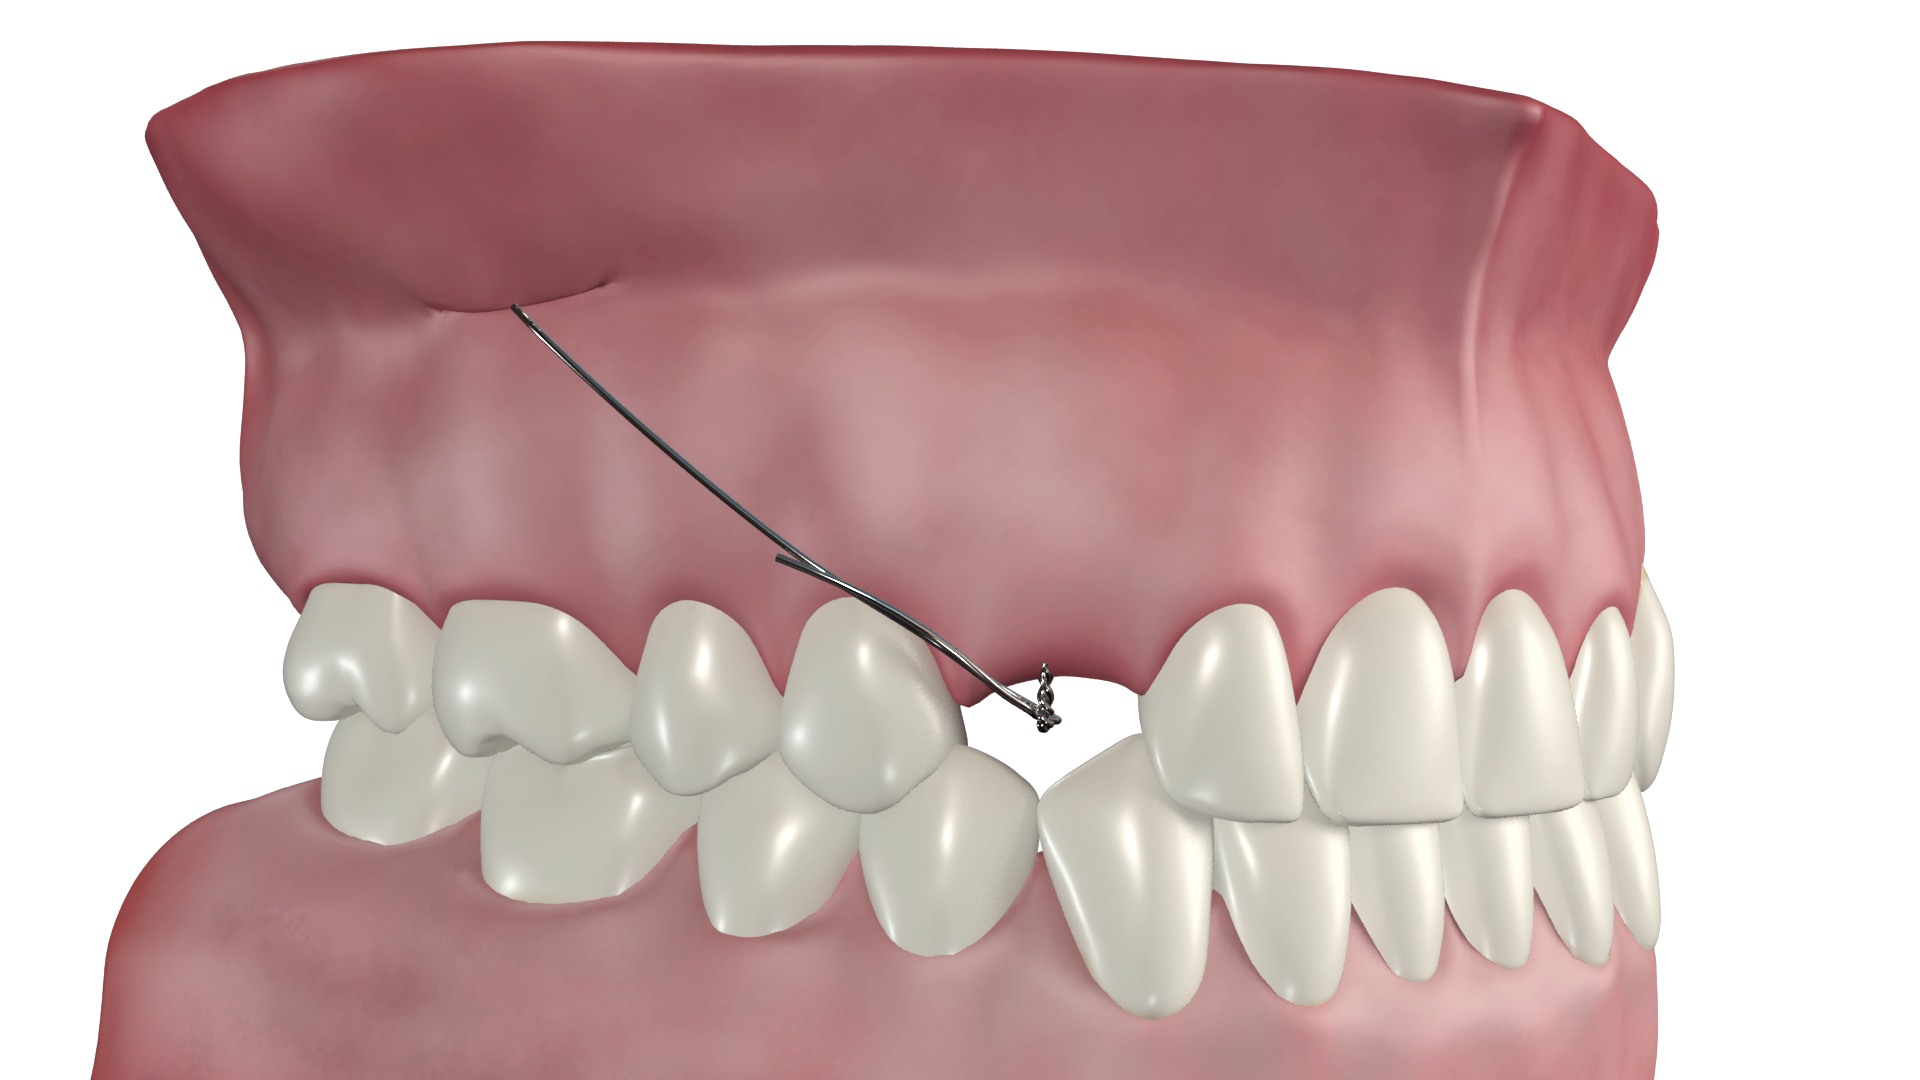

- une ou deux micro-vis en alliage de titane TiAl6V4, autoforeuse et autopréhensible sur le tournevis dédié, enfouie en fond de vestibule au-delà des apex

- une connectique en alliage CTnox spécialement conçu et développé pour le système CT8, attachée à la vis et émergeant au centre du vestibule dans une muqueuse non kératinisée. Le fil est plaquée contre la corticale osseuse sous la muqueuse et au delà il longe la gencive ce qui en fait un dispositif très discret et faiblement invasif pour le patient.

- Vissage de la ou des vis et plaquage du fil contre la corticale osseuse

Le geste peut être réalisé quasiment en aveugle car il n’y a aucun risque anatomique pour les structures sous-jacentes.

Le bras de la connectique est libéré de l’encoche du tournevis par un simple mouvement de doigt dès que la vis commence être vissée dans la corticale.

Le vissage est réalisé jusqu'à ce que la vis paraisse entraîner la connectique dans sa rotation. Elle est alors légèrement desserrée pour permettre de la repositionner avant son serrage final.